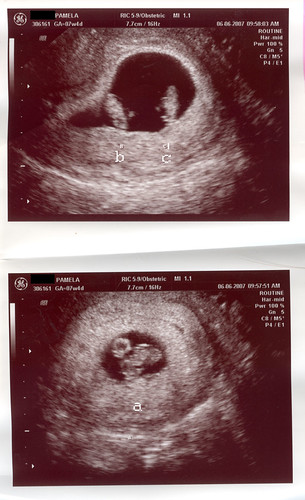

Three years ago, I got knocked up, times three: